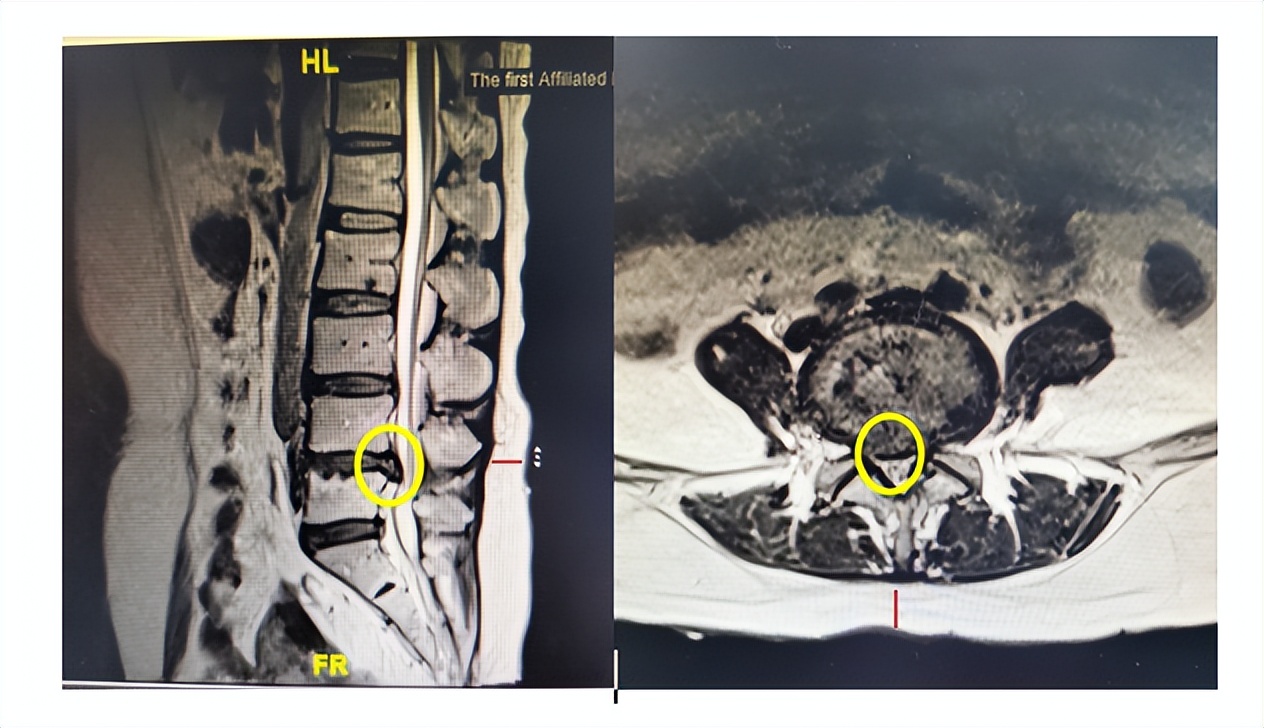

黄圈标记为脱出的间盘组织压迫神经

2023年4月,哈尔滨医科大学附属第一医院骨科一病房收治了一位20岁,身高192cm,体重却高达310斤的大男孩小杨。小杨入院时腰部及左左腿疼痛剧烈,无论坐下还是站立都痛得难以忍受,根本不能正常行走。经详细检查发现小杨的腰5-骶1椎间盘巨大突出伴钙化,压迫神经,诊断为腰椎间盘突出症、腰椎管狭窄症。